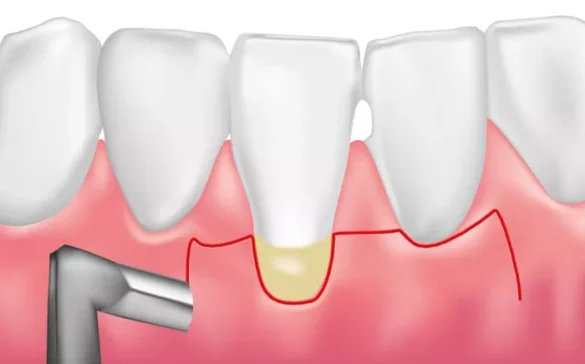

Your dentist will perform scaling and root planing to remove tartar and bacteria from tooth surfaces and below the gum line. This deep cleaning smooths root surfaces to help gums reattach to teeth. Multiple visits may be needed depending on the severity. Regular dental cleanings every 3-6 months help prevent gum disease from returning.

If periodontitis has caused deep pockets or bone loss, surgical treatments may be necessary. Procedures include flap surgery to clean infected areas or bone and tissue grafts to regenerate lost structures. Laser therapy is another option to remove diseased tissue and promote healing. Your periodontist will recommend the best treatment based on your condition.